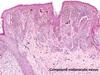

Identify

Identify

Identify

symmetrical

melanocytes get smaller with depth

would not expect to see atypia or mitoses

in a benign nevus

Benign Nevus Histology Characteristics

6 listed

Benign Naevia melanocytes get smaller as you go down